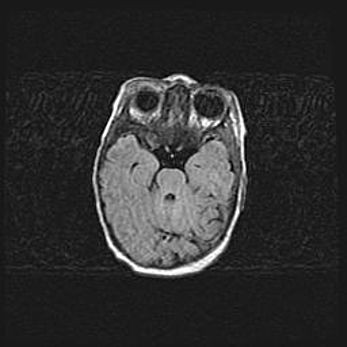

Церебральная ишемия II.

Возраст: 5 дней

Вес: 3400 г

Пол: женский

Окружность головы: 35 см

Срок гестации: 39 недель

Церебральная ишемия – это заболевание, характеризующееся недостаточностью (гипоксией) либо полным прекращением (аноксией) снабжения мозга кислородом по причине закупорки одного или нескольких сосудов. Это приводит к  что метаболическим расстройствам различной степени тяжести в тканях головного мозга, развитию коагуляционных некрозов и гибели нейронов.